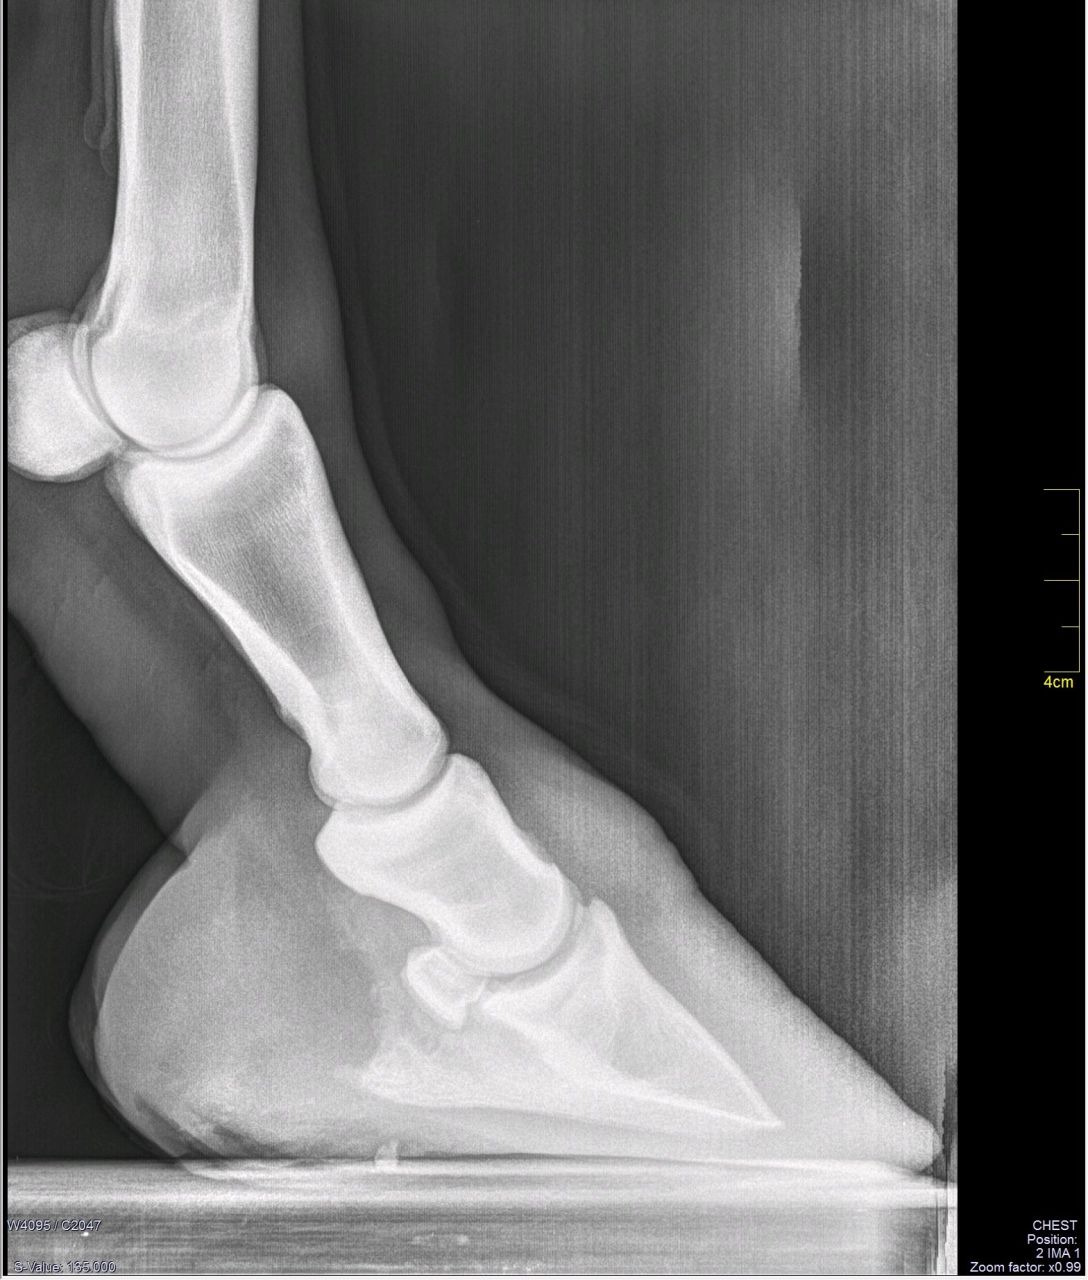

· Ham Clock looks great and is a real enrichment for every ham radio operator · RADIOGRAPHIE DE LA HANCHE DE FACE 4 juin 17 Dans "BANQUES D'IMAGES" RADIOGRAPHIE DU POIGNET DE FACE 4 juin 17 Dans "BANQUES D'IMAGES" Publié dans BANQUES D'IMAGES , Non classé , RADIOGRAPHIES Navigation des articles1) des radios en position debout FACE et PROFIL du pied EN ENTIER Elles permettent de mesurer les angles qui confirment la déformation en pied plat Le cliché de profil debout cherche à évaluer la divergence du talus et du calcaneum (ou inclinaison de l'astagale par rapport au calcaneum)

En effet, le pied étant un organe de la locomotricité (marche), l'analyse n'a d'intérêt que lorsqu'il est en appui Une radiographie du pied en charge nous permettra d'analyser précisément l'architecture de votre pied dans le cadre du bilan radiologiqueSearch query Yahoo Help;2,371 Free images of Radio Related Images microphone music sound audio retro technology headphones fireworks vintage radio 312 55 Radio Cassette Speaker 718 134 Car Traffic Man Hurry 409 63 Microphone Music Sound 310 90 Open Fire Fire Embers 131 162 Headphones Radio Music 167 31 Shower Of Sparks Light 130

· Les radiologues de centre d'imagerie IMBM, situé dans le quartier Batignolles Montmartre, dans le 18ème, réalisent votre radio de la cheville ou des pieds à ParisCet examen est réalisé en cas de douleurs, de traumatisme, de chute, de suspicion d'arthrose Nous réalisons les clichés conventionnels debout, de face, profil, avec les clichés en charge afin de réaliser lesPour une étude statique de vos pieds, les radiographies se réalisent debout, le pied sur le capteur Le profil de pied se réalise sur un marchepied spécifique Il vous faudra monter 3 marches et placer vos pieds de part et d'autre d'une gouttière où sera placé le capteur WIFI · Pour prendre une photo en projection directe (plantaire arrière) le pied est placé sur la semelle en position couchée, les jambes pliées au niveau des genoux Une image de chaque doigt sur le côté est réalisée avec la pose latérale du pied et